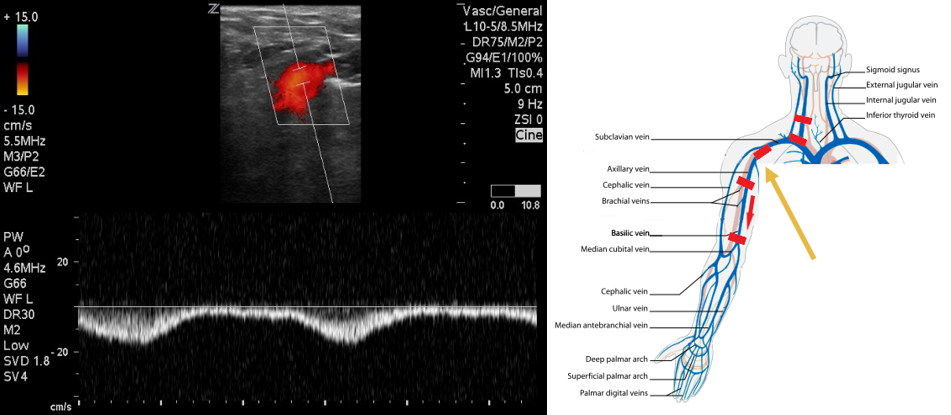

- Next move to the axilla on the same side. With the patient in supine position, have them place their hand on their head to expose the area of interest.

- Identify the subclavian vein as it crosses from the axilla. This area can be difficult to compress. Use color flow in long axis to identify filling defects. Use pulsed wave Doppler to identify normal versus abnormal flow patterns.

- Figure 5. Pulsed wave Doppler over axillary vein demonstrates biphasic flow.